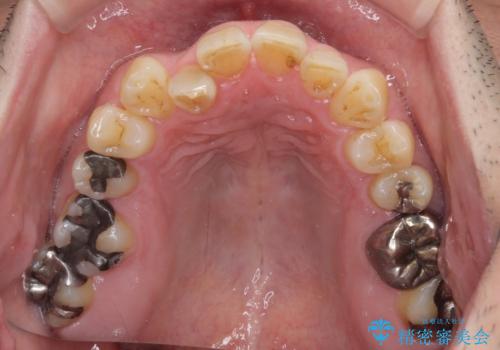

- 近医にてブリッジ治療を行った歯が痛くてたまらないとのことで来院された患者様です。

診察を行ったところ、奥の土台になっている歯は神経組織が失活しており、根尖部に病変があり、そこが原因で痛みを生じている状態でした。

根管治療を行うためにブリッジを除去したところ、むし歯が歯肉の奥深くにあまで及んでいたため、歯周外科処置によりむし歯が歯肉縁より浅い位置へと改善することとしました。

ここまでの治療を提案したところで、折角なのでしっかり治療を行いたいとのことで、前歯のデコボコやクロスバイトを改善するための矯正治療を行うこととしました。

まずは奥歯の痛みを改善し、その後矯正治療を行い、最後にオールセラミックブリッジによる補綴治療を行うこととしました。